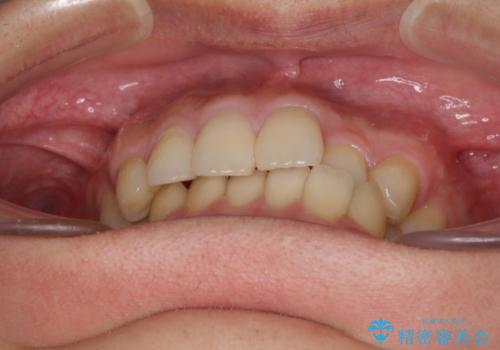

前歯のクロスバイトと抜歯が必要な奥歯の虫歯 インビザラインとインプラント治療

- 前歯のクロスバイトと、大学生のころから放置している虫歯を気にして来院された患者様です。

マウスピースでの矯正治療を希望されていましたが、前歯のクロスバイトは不十分な仕上がりや歯髄壊死などのリスクが高くなるため、術前にワイヤーで大まかに整えてからインビザラインにて矯正治療を行うこととしました。

奥歯の虫歯は抜歯が必要であったので、矯正治療前に抜歯をし、矯正治療と並行してインプラントによる補綴治療を行うこととしました。